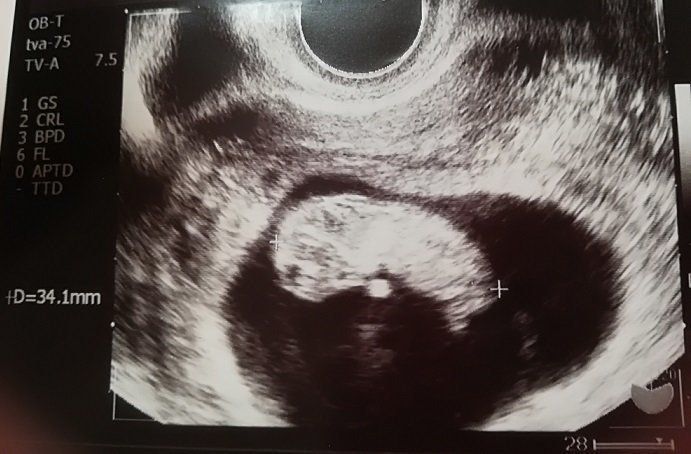

妊娠9週目のエコー写真

「もう、人の形をしている!」と驚きました。妊娠と同時に、里帰り先の産院を予約しました。その喜びをすべて吹っ飛ばしたのが、“つわり”。程度は違うものの皆さん経験するようですが、私は、家のビニール袋がすべてなくなるまで吐いてしまうという重症でした。内科で毎日点滴を受けながら乗り切り「母が食べられなくても、赤ちゃんて育つものだなぁ」と、感心しながら健診を受けていました。